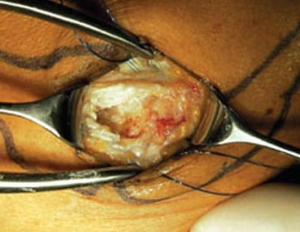

Hierbei wird in der von uns bevorzugten Technik nach Nirschl der krankhaft veränderte Anteil der Sehne des Musculus extensor carpi radialis brevis (ECRB) entfernt und der Knochen im Bereich des Epicondylus mehrfach angebohrt, so dass Blut heraustritt (Abb. 58). Durch die im Blut enthaltenen Zellen und Stoffe kommt es dann nach Naht der Sehnenansätze zu einer erneuten Heilung des Gewebes auf dem Epicondylus. Dieser Eingriff erfolgt in einer offenen Technik mit einem Hautschnitt von ca. 4 cm.